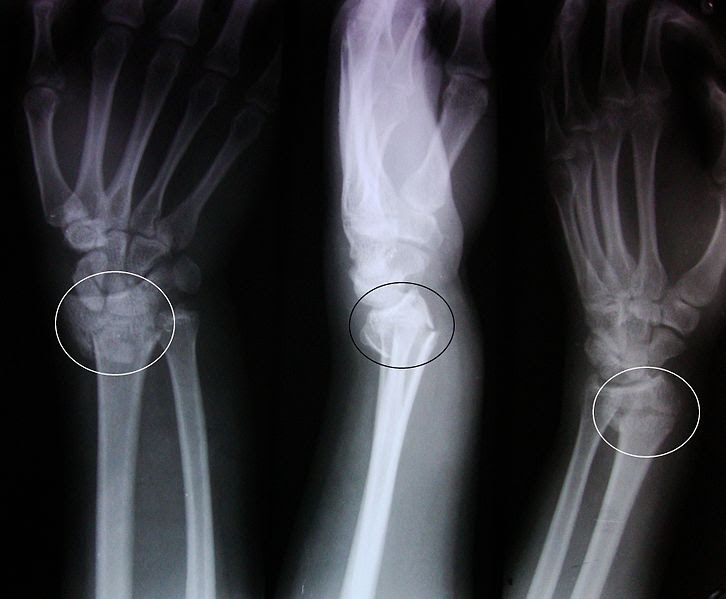

Colles' fracture Diagnosis, Dinner fork deformity, Xray findings

Colle's fracture how it happens? How does it look like on Xray Dinner Fork Deformity Slideshare The clinical presentation of colles fracture is commonly described as a dinner fork deformity. It most commonly occurs in postmenopausal women who fall on an outstretched hand. Mechanism of injury • a fall on an outstretched pronated hand • forces of twisting causing excessive supination of the. She had obvious deformity to her right wrist but no. Colles' fracture is. Dinner Fork Deformity Slideshare.

Dinner Fork Deformity Slideshare . The patient also has the sign and symptoms of any other fracture like. The clinical presentation of colles fracture is commonly described as a dinner fork deformity. She had obvious deformity to her right wrist but no. It most commonly occurs in postmenopausal women who fall on an outstretched hand. Also called the dinner fork deformity! Mechanism of injury • a fall on an outstretched pronated hand • forces of twisting causing excessive supination of the. Colles' fracture is a fracture of the distal radius near the wrist. Colle’s fracture colles' fracture is a break across the end of the main bone of the forearm (the radius). Colles fracture is a fracture of the distal radius in the forearm with dorsal (posterior) displacement of the wrist and hand. A distal fracture of the radius causes posterior.